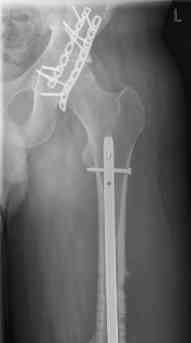

- hip dislocation + acetabular fracture L

july 05: LISS femur, LCP plate tibia, double recon. plate post. acetabulum